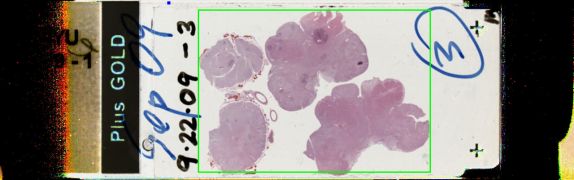

Slide Image:

view high resolution slide image

The 1100 gram brain showed multiple infarcts, with attenuated white matter and cortex.  There cerebellum contain infarcts and the dentate nucleus showed marked neuronal loss, with perineuronal vacuolation, and vacuoles in the remaining neurons.  There was hippocampal sclerosis.  A section of medulla showed hypertrophy of the inferior olivary nucleus.